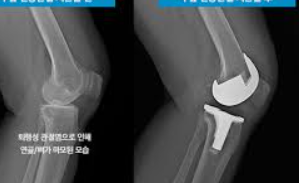

인공 관절 수술은 퇴행성 관절염이나 다른 관절 손상으로 인해 자연 관절이 기능을 상실했을 때 고려되는 치료 방법입니다. 이 수술은 손상된 관절을 인공 재료로 만든 새로운 관절로 교체하는 과정을 포함합니다. 수술 비용은 다양한 요인에 따라 달라질 수 있으며, 환자의 나이, 수술의 복잡성, 사용되는 재료의 종류, 병원의 위치와 수준 등에 따라 천차만별입니다. 일반적으로, 수술 비용은 수술 전 검사비, 수술비, 입원비 등을 포함하여 수백만 원에서 천만 원 이상이 될 수 있습니다. 또한, 환자의 건강보험 적용 여부에 따라 실제 환자가 부담해야 하는 비용은 크게 달라질 수 있습니다. 건강보험 적용을 받을 수 있는 경우, 환자의 부담금은 상당히 줄어들 수 있으며, 특정 조건을 충족하는 경우 추가적인 정부 지원을 받을 수도 있습니다. 수술 후에는 일정 기간 동안 재활 치료가 필요할 수 있으며, 이는 전체 치료 비용에 영향을 미칠 수 있습니다. 인공 관절 수술은 환자의 삶의 질을 향상시킬 수 있는 중요한 수단이 될 수 있지만, 수술을 결정하기 전에 비용과 잠재적인 결과에 대해 의료 전문가와 상세히 상담하는 것이 중요합니다.

인공 관절 수술은 관절의 퇴행성 변화, 외상, 또는 다른 질환으로 인해 손상된 관절을 인공적인 재료로 만든 관절로 교체하는 의료 절차입니다. 이 수술은 주로 무릎, 고관절, 어깨 관절 등에 적용되며, 환자의 삶의 질을 향상시키고 통증을 감소시키는 데 목적이 있습니다.

인공 관절 수술의 종류는 크게 두 가지로 나뉩니다: 전치환술과 부분치환술입니다. 전치환술은 손상된 관절 전체를 인공 관절로 교체하는 방법이며, 부분치환술은 손상된 관절의 일부만을 교체하는 방법입니다. 환자의 상태와 필요에 따라 적절한 수술 방법이 선택됩니다.

전치환술은 관절의 변형이 심하거나 손상 부위가 넓은 경우에 주로 사용됩니다. 이 수술은 관절의 안쪽과 바깥쪽 모두를 인공 관절로 바꿔줌으로써, 통증을 줄이고 관절의 기능을 회복시키는 데 도움을 줍니다.

반면, 부분치환술은 관절의 손상이 비교적 제한적인 경우에 적합합니다. 이 수술은 절개 부위가 작고 회복이 빠르며, 무릎 운동 범위의 제한이 적다는 장점이 있습니다. 특히, 연골 내측만 손상된 경우나 십자인대 기능이 정상인 경우에 시행됩니다.